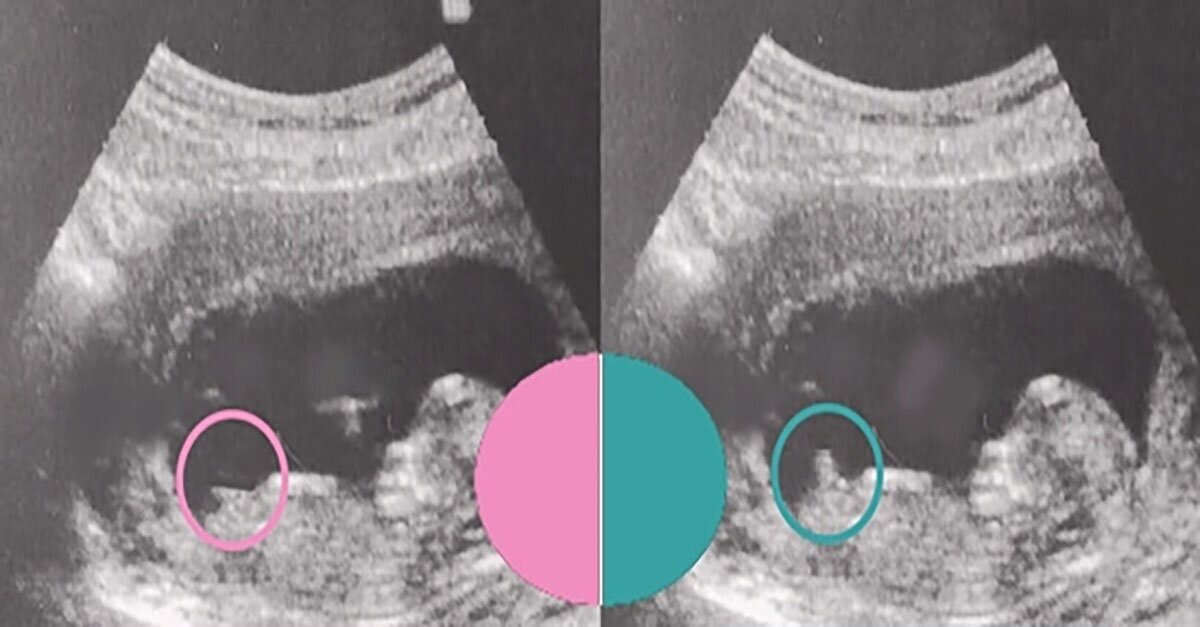

Особенности УЗИ при определении пола ребенка

Раздел: Идеи и советы